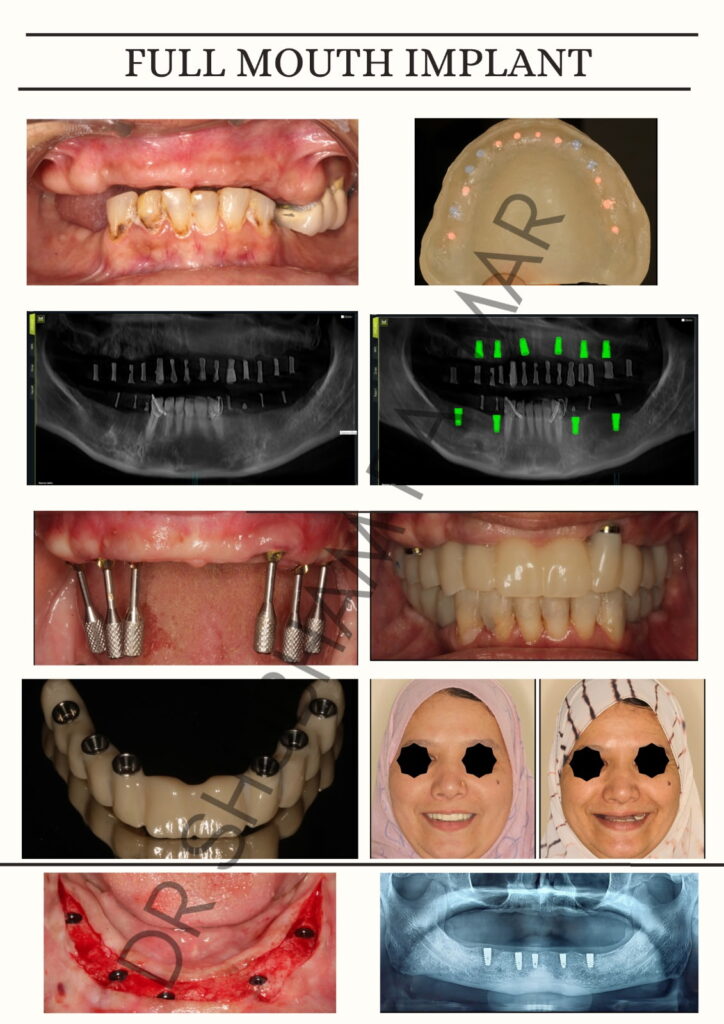

With 1.5 years of focused clinical experience, Dr. Shubham has developed expertise in implantology and full mouth rehabilitation, managing both routine and complex prosthodontic cases with a focus on function, aesthetics, and long-term stability. His approach is rooted in prosthetically driven implant planning, ensuring optimal outcomes from surgical placement to final prosthesis.

He is particularly skilled in full-arch implant solutions (All-on-4 / All-on-6), management of implant complications, and rehabilitation of failed cases, offering predictable and structured solutions even in challenging scenarios. Known for his strong case presentation skills and patient-centric communication, he consistently contributes to improved case acceptance and clinical success.

- All-on-4 / All-on-6 Solutions β Immediate loading, full-arch transformations with predictable outcomes

- Full Mouth Implant Prosthetics β From planning to final prosthesis with long-term stability focus

Full Mouth Implants